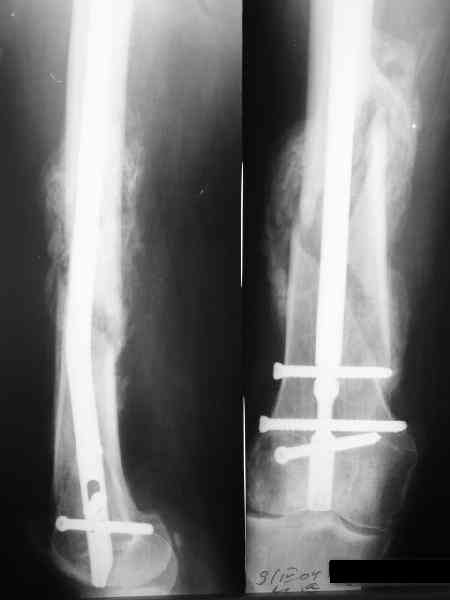

Как обещал, выкладываю рентгенограммы нашего пациента.

Пациенту М., 30-ти лет, 1,5 года назад в одной из московских больниц был выполнен остеосинтез бедренной кости штифтом UFN (диаметр штифта 9 мм).

К нам больной поступил с признаками ложного сустава бедренной кости, перелома

штифта и дистального блокирующего винта (images 1,2,3).

27 марта выполнено удаление блокирующих винтов (сломанный винт пришлось высверливать цапфен-бором), сломанного штифта (дистальный фрагмент удален через канал, образованный разверткой из коленного сустава - image 4),

рассверливание костно-мозгового канала, реостеосинтез штифтом UFN (при проведении штифта в дистальном отломке мы использовали поляризующий винт, диаметр штифта 10 мм). После операции в связи гемартрозом дважды (на 1 и 3 сутки) выполняли пункцию коленного сустава. Сейчас признаков скопления жидкости в полости сустава нет. Послеоперационные рентгенограммы - images 5, 6, 7.